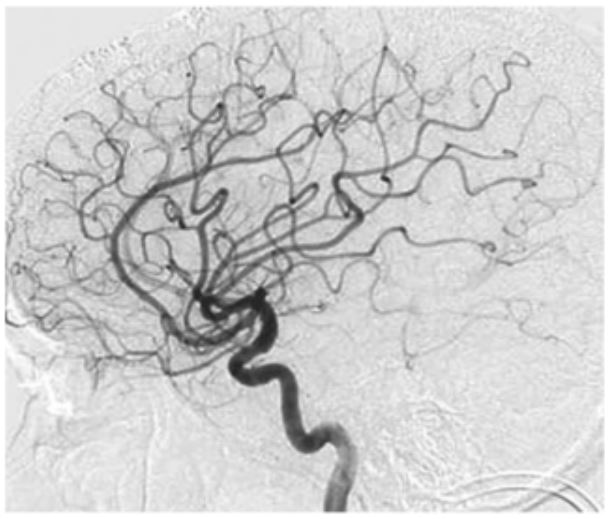

- 우리 뇌의 바닥 쪽에 있는 뇌혈관 중 내경동맥의 끝부분과 이와 연결된 대뇌동맥고리(월리스 동맥륜)가 안쪽부터 두꺼워지면서 혈관이 막히면서 이런 혈관을 대신하기 위해 가느다란 혈관들이 생겨나는 희귀병을 얘기합니다.

- 1960년대 일본에서 뇌혈관 조영술을 연구하다 발견해 혈관 모양이 연기가 모락모락 올라가는 것처럼 보인다고 하여 모야모야병이 이라고 이름을 붙였습니다.